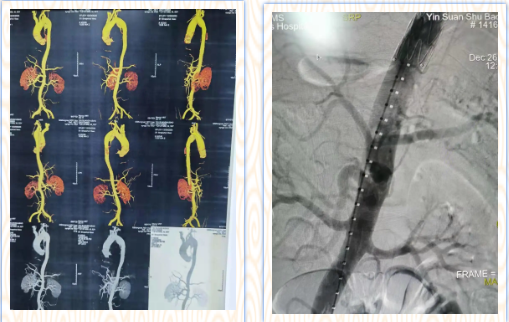

12月26日,我院胸外科介入团队在甘肃省人民医院心血管专家的指导下,成功为一位主动脉夹层患者实施了微创介入治疗,挽救了一条鲜活的生命,此项技术的开展填补了我市主动脉夹层治疗领域的空白。

患者入院后,胸外科主任尹义学高度重视,随即邀请麻醉科、ICU、介入科同事进行病情讨论,最终决定行主动脉腔内隔绝术治疗。经过科室严谨的术前准备后,于甘肃省优势学科医联体平台,邀请甘肃省人民医院心血管外科尤涛教授及团队前来会诊指导手术,手术历时2小时顺利完成,取得圆满成功。

主动脉夹层是主动脉疾病里最凶险的一个疾病,起病非常急,血管外膜一旦破裂,患者大出血就会死亡。我市由于交通不便,许多主动脉夹层患者在转院途中不幸身亡,为了能够尽可能挽救这一部分患者的生命,我院领导与西京医院心血管外科建立合作平台,先后派出我院医务人员进行学习,引进技术,并积极参与甘肃省优势学科联盟建设,让患者能够在家门口得到有效救治,减轻了患者外出求医的种种不便,而且进一步提升了我院的专业技术水平与服务能力。